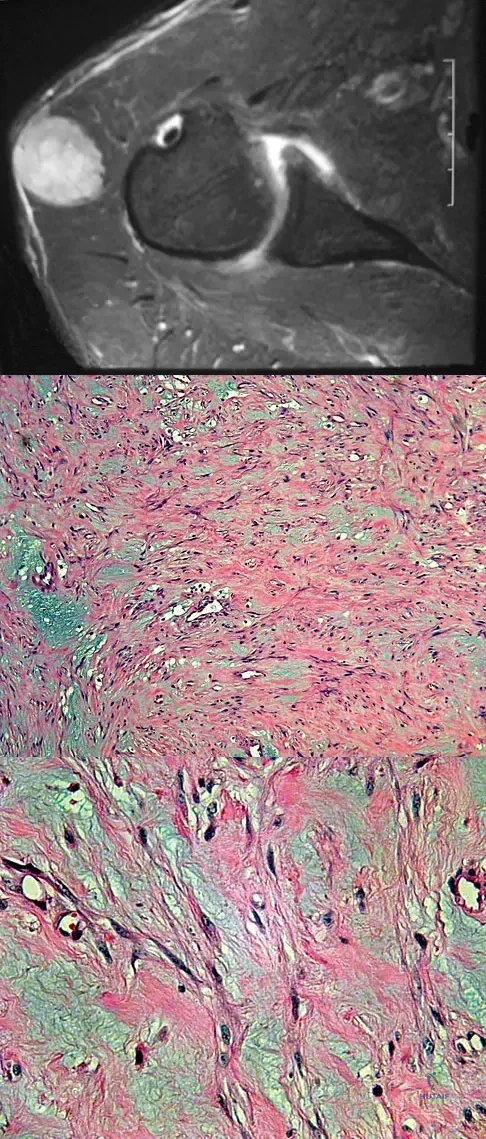

A 37-year-old man pulled his hamstring playing softball 3 weeks ago. The patient had not noted any mass prior to his injury. MRI scans of the posterior thigh are shown in Figures 4a and 4b. Figure 4c shows the biopsy specimen from a needle biopsy. What is the most likely diagnosis?

Malignant fibrous histiocytoma (MFH) is the most common soft-tissue sarcoma. MFH typically presents as a large mass, deep to the fascia with heterogeneous signal on MRI. The MRI scans show a heterogeneous lesion in the posterior thigh. There is significant high signal uptake on the T2-weighted image. The histology shows malignant histiocytic cells with marked atypia and pleomorphism. Histology of a hematoma would show only old hemorrhage and some granulation tissue. Lipoma and liposarcoma are both seen as a fat-containing lesion on histology. No significant fat tissue is seen in this histologic specimen. Histology of myositis ossificans would show bone formation. Simon SR (ed): Orthopaedic Basic Science. Rosemont, IL, American Academy of Orthopaedic Surgeons, 1994, pp 219-276.